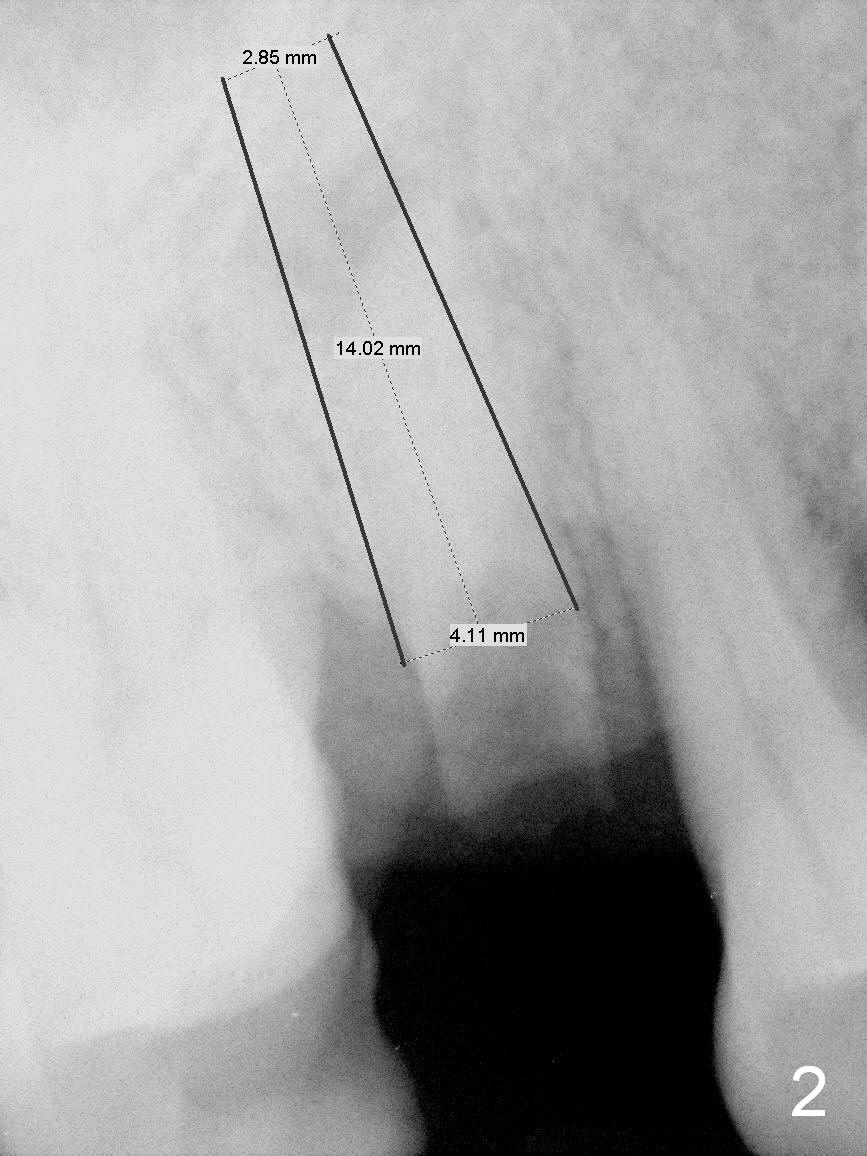

A 62-year-old man (CZ) has had chronic periodontitis. A month ago, five immediate implants were placed in the lower anterior region. Fig. 1 shows a PA taken 4 years ago: #4 residual root and #6 severe bone loss. A 4.1x14 mm bone-level implant is planned immediately after extraction (Fig.2). Clinically, the residual root is oval in shape (Fig.3 dashed line). The implant is placed as palatal as possible after socket treatment with 2% Xylocaine/1:50,000 Epinephrine (Fig.4). In addition, the osteotomy may have to be established in the distal wall, since the root tip tilts mesially (Fig.1). Take the 1st intraop PA after 2 mm pilot drill.